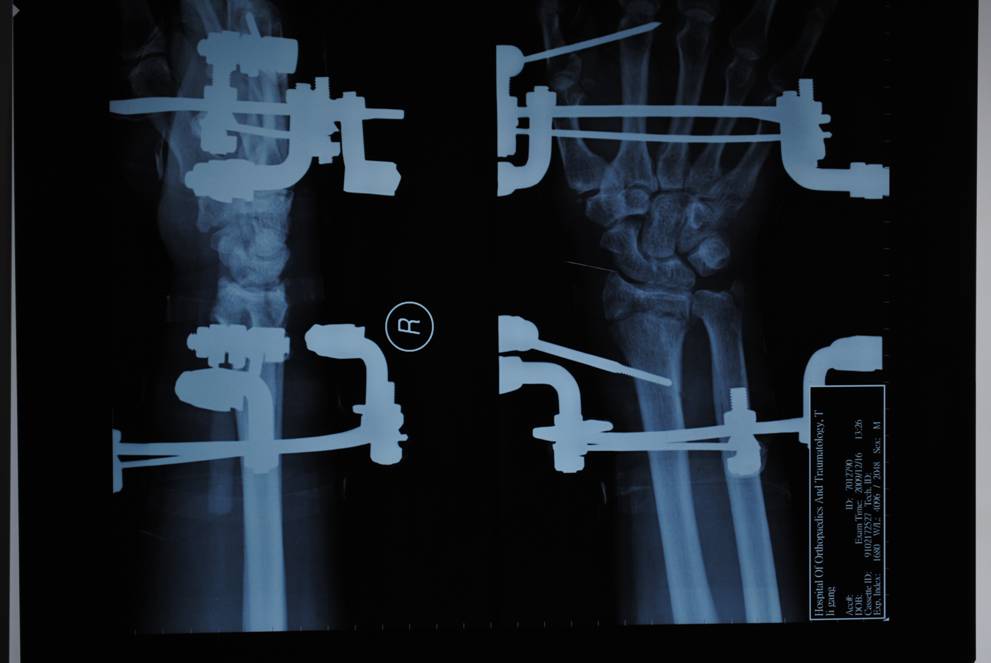

專利腕架

1、一種組合式腕關(guān)節(jié)三維牽引固定架,其特征在于:主要包括一根碳纖維和一根硬鋁連接桿和兩只弧型環(huán),兩只弧型環(huán)沿弧線方向的端面上均設(shè)有多個(gè)通孔,每根碳纖維連接桿的兩端分別鎖緊連接于兩只弧型環(huán)相對(duì)應(yīng)的通孔上,每個(gè)弧型環(huán)上均設(shè)有兩只鎖針螺釘,鎖針螺釘靠近其螺栓部分的端面上均設(shè)有穿針槽,鎖針螺釘?shù)穆菟ń?jīng)螺母鎖緊在弧型環(huán)上,第一克氏針依次穿過第一弧型環(huán)上的第一鎖針螺釘穿針槽、掌骨頸、第二鎖針螺釘穿針槽并由螺母鎖緊第一、二鎖針螺釘?shù)穆菟▽⒌谝豢耸厢槈壕o在第一弧型環(huán)上,第二克氏針依次穿過第二弧型環(huán)上的第三鎖針螺釘穿針槽、橈骨、第四鎖針螺釘穿針槽并由螺母鎖緊第三、四鎖針螺釘?shù)穆菟▽⒌诙耸厢槈壕o在第二弧型環(huán)上。

橈骨遠(yuǎn)端骨折術(shù)前

橈骨遠(yuǎn)端骨折術(shù)后

五研獨(dú)家產(chǎn)品組合式腕關(guān)節(jié)骨外定架,具有專利保護(hù)

組裝簡便,穿針便捷,適合各種橈骨遠(yuǎn)端骨折及腕部矯形。斷端無X線遮擋。